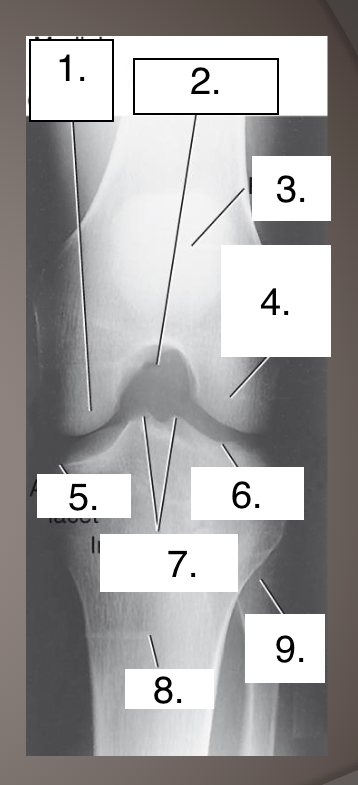

Projection?

Label?

Incondylar fossa

Medial femoral condyle

Intercondylar fossa

Patella

Lateral femoral condyle

Articular facet

Articular facets

Intercondylar eminence

Tibia

Fibular head